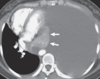

Fig. 3.1 Atelectasia obstructiva (reabsorbente) del lóbulo superior izquierdo por carcinoide endobronquial. Una tomografía computarizada con contraste muestra un tumor (flecha curvada) que obstruye el bronquio del lóbulo superior izquierdo con atelectasia completa del lóbulo superior izquierdo asociada (flechas rectas). Obsérvese el desplazamiento anterior y medial de la fisura principal izquierda (flechas rectas).